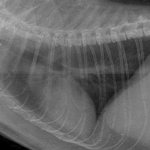

Для определения наличия жидкости в грудной полости используется УЗИ. Выпот видно на снимках и рентгенограммах. Врач также проводит прослушивание и постукивание, что требует специальных навыков и знаний.

- рентгенографию грудной клетки;

Диагностика основывается на клинических признаках, рентгенологическом исследовании и УЗИ.